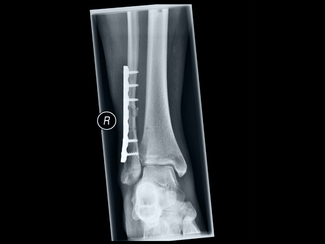

In der Röntgendiagnostik werden die drei Techniken Röntgenaufnahmen, Röntgendurchleuchtungen und Computertomographien (CT) unterschieden.